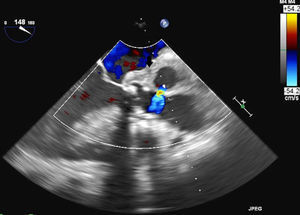

Sixty-six year-old patient with a mechanical aortic prosthesis implanted two months ago, who recently experienced a deterioration in his level of consciousness and a sudden-onset fever of up to 39°C, along with a bluish nodular lesion in the fifth digit (little finger) of his left hand. The brain CAT scan performed revealed a parietal intraparenchymal hemorrhage, of which blood cultures were taken (with a positive result for Staphylococcus aureus). Furthermore, the transthoracic echocardiogram (TTE) carried out showed a poorly differentiated hyperechogenic image at the level of the prosthetic valve. Based on the above findings, a transesophageal echocardiography (TEE) was also performed revealing the presence of a metallic aortic valve prosthesis associated with periaortic thickening (arrow, Fig. 1) along with images of cavitated lesions in the posterior end of the aortic root (asterisk, Fig. 2), one of which was seen to come into contact with it, thus being suggestive of a complicated endocarditis. Additionally, a cardiac CAT scan showed a 9-mm heart wall defect coming into contact with a 9×6×5.5-cm collection, as well as contrast media extravasation suggestive of a broken pseudoaneurysm contained by the epicardium (arrow, Fig. 3). This case report brings to light the key role of TEE in detecting cases of endocarditis.